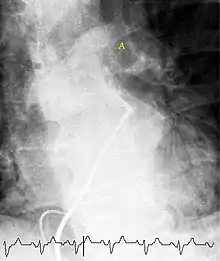

Ventilation/perfusion scan

(A) After inhalation of 20 mCi of Xenon-133 gas, scintigraphic images were obtained in the posterior projection, showing uniform ventilation to lungs.

(B) After intravenous injection of 4 mCi of Technetium-99m-labeled albumin, scintigraphic images shown here in the posterior projection. This and other views showed decreased activity in multiple regions.

A ventilation/perfusion scan (or V/Q scan or lung scintigraphy) shows that some areas of the lung are being ventilated but not perfused with blood (due to obstruction by a clot).[17] This type of examination is as accurate as multislice CT, but is less used, due to the greater availability of CT technology. It is particularly useful in people who have an allergy to iodinated contrast, impaired kidney function, or are pregnant (due to its lower radiation exposure as compared to CT).[62][63][64] The test can be performed with planar two-dimensional imaging, or single photon emission computed tomography (SPECT) which enables three-dimensional imaging.[55] Hybrid devices combining SPECT and CT (SPECT/CT) further enable anatomic characterization of any abnormality.[65]